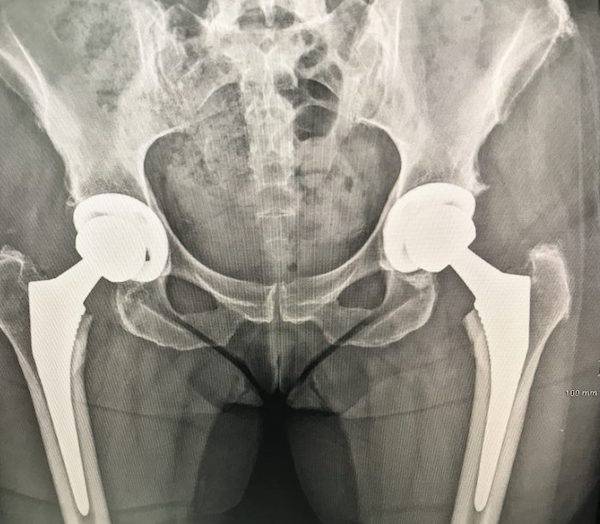

New Hips, Grace & Frankie, Healed Swiftly With Vegan Eating

I get to be 70 in two months. But my hip cartilage only lasted to about

60, when it started its decline. X-rays a year ago showed bone-on-bone with

little range left in my motion.

I refused to hit the big 7-0 coddling painful hips with pill popping, so I

had total joint replacements last May and July. I simple-size anything I can

(www.simplesizeme.net). With health and mobility involved, I bet on the

best: a good surgeon, food as medicine, and physical therapy fit for an

Olympian.